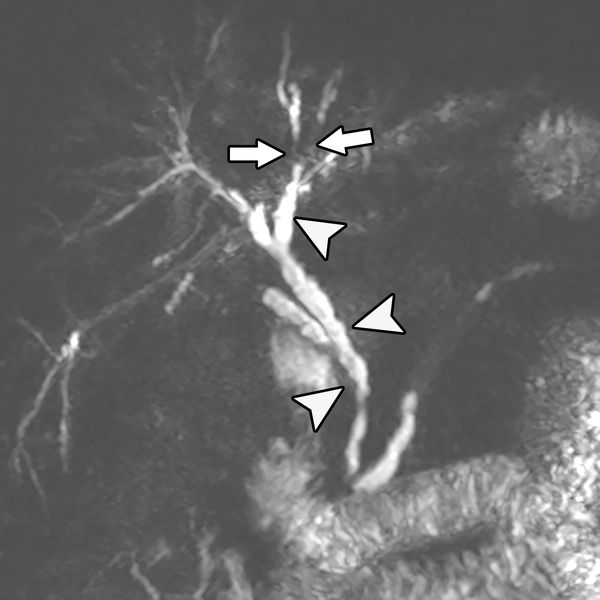

Фотографии и изображения, связанные с симптомами первичного склерозирующего холангита